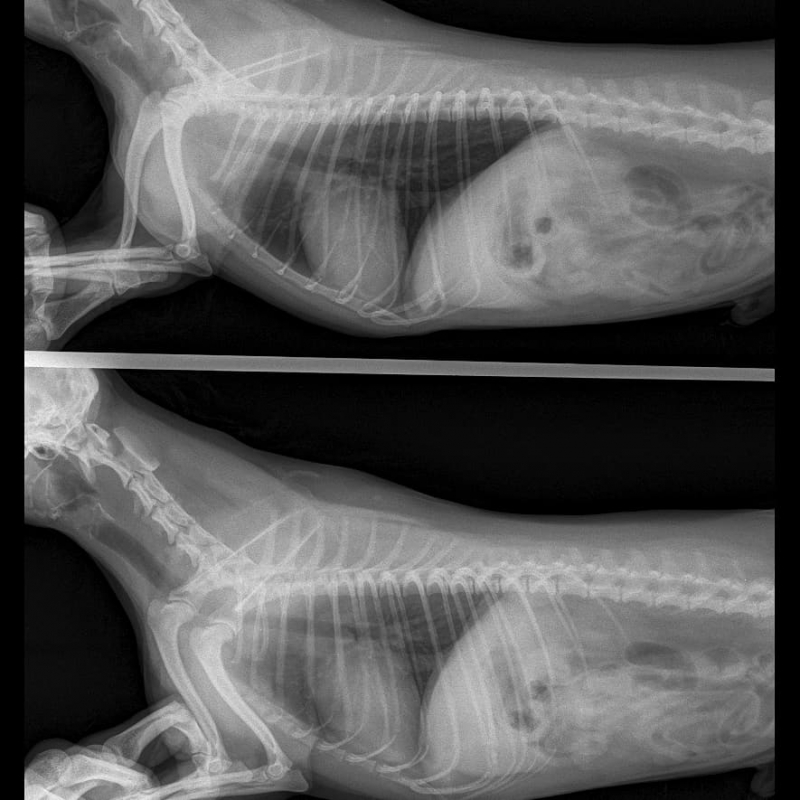

Коллапс трахеи кашель

Коллапс трахеи кашель 117 фото